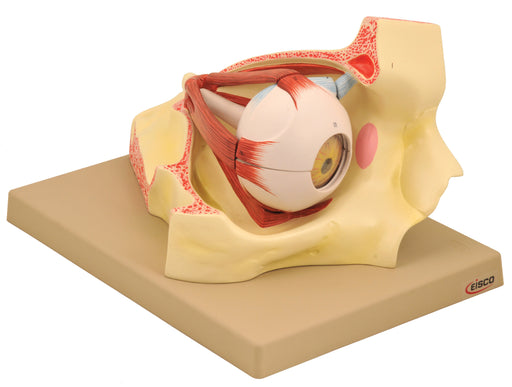

Model, Human Eye in Orbit, 9 Part, Dissectable, 3 Times Enlarged

The highly detailed 9-part dissectable human eye model (enlarged 3 times) allows students to examine the extremely complex anatomical structures wi...

View full detailsAM30AS -